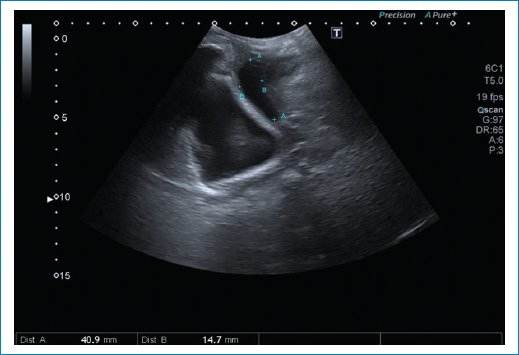

• – Cistocele: con el examen físico solamente podemos evaluar un prolapso de la pared anterior de la vagina; sin embargo, con las imágenes podemos diferenciar entre un cistouretrocele que se asocia a incontinencia de orina y un cistocele con ángulo retrovesical intacto con síntomas de obstrucción al vaciado y baja probabilidad de incontinencia de orina. También puede ser que el prolapso de la vagina anterior sea por un divertículo uretral, quiste de Gartner o un enterocele anterior. El punto de corte para determinar el descenso de la vejiga es 10 mm por debajo de la línea pubiana que se traza perpendicular a la sínfisis pubiana3 (Fig. 7).

Figura 7. Se observa un descenso de la pared posterior vesical por debajo de la línea pubiana, con ángulo retrovesical cerrado.